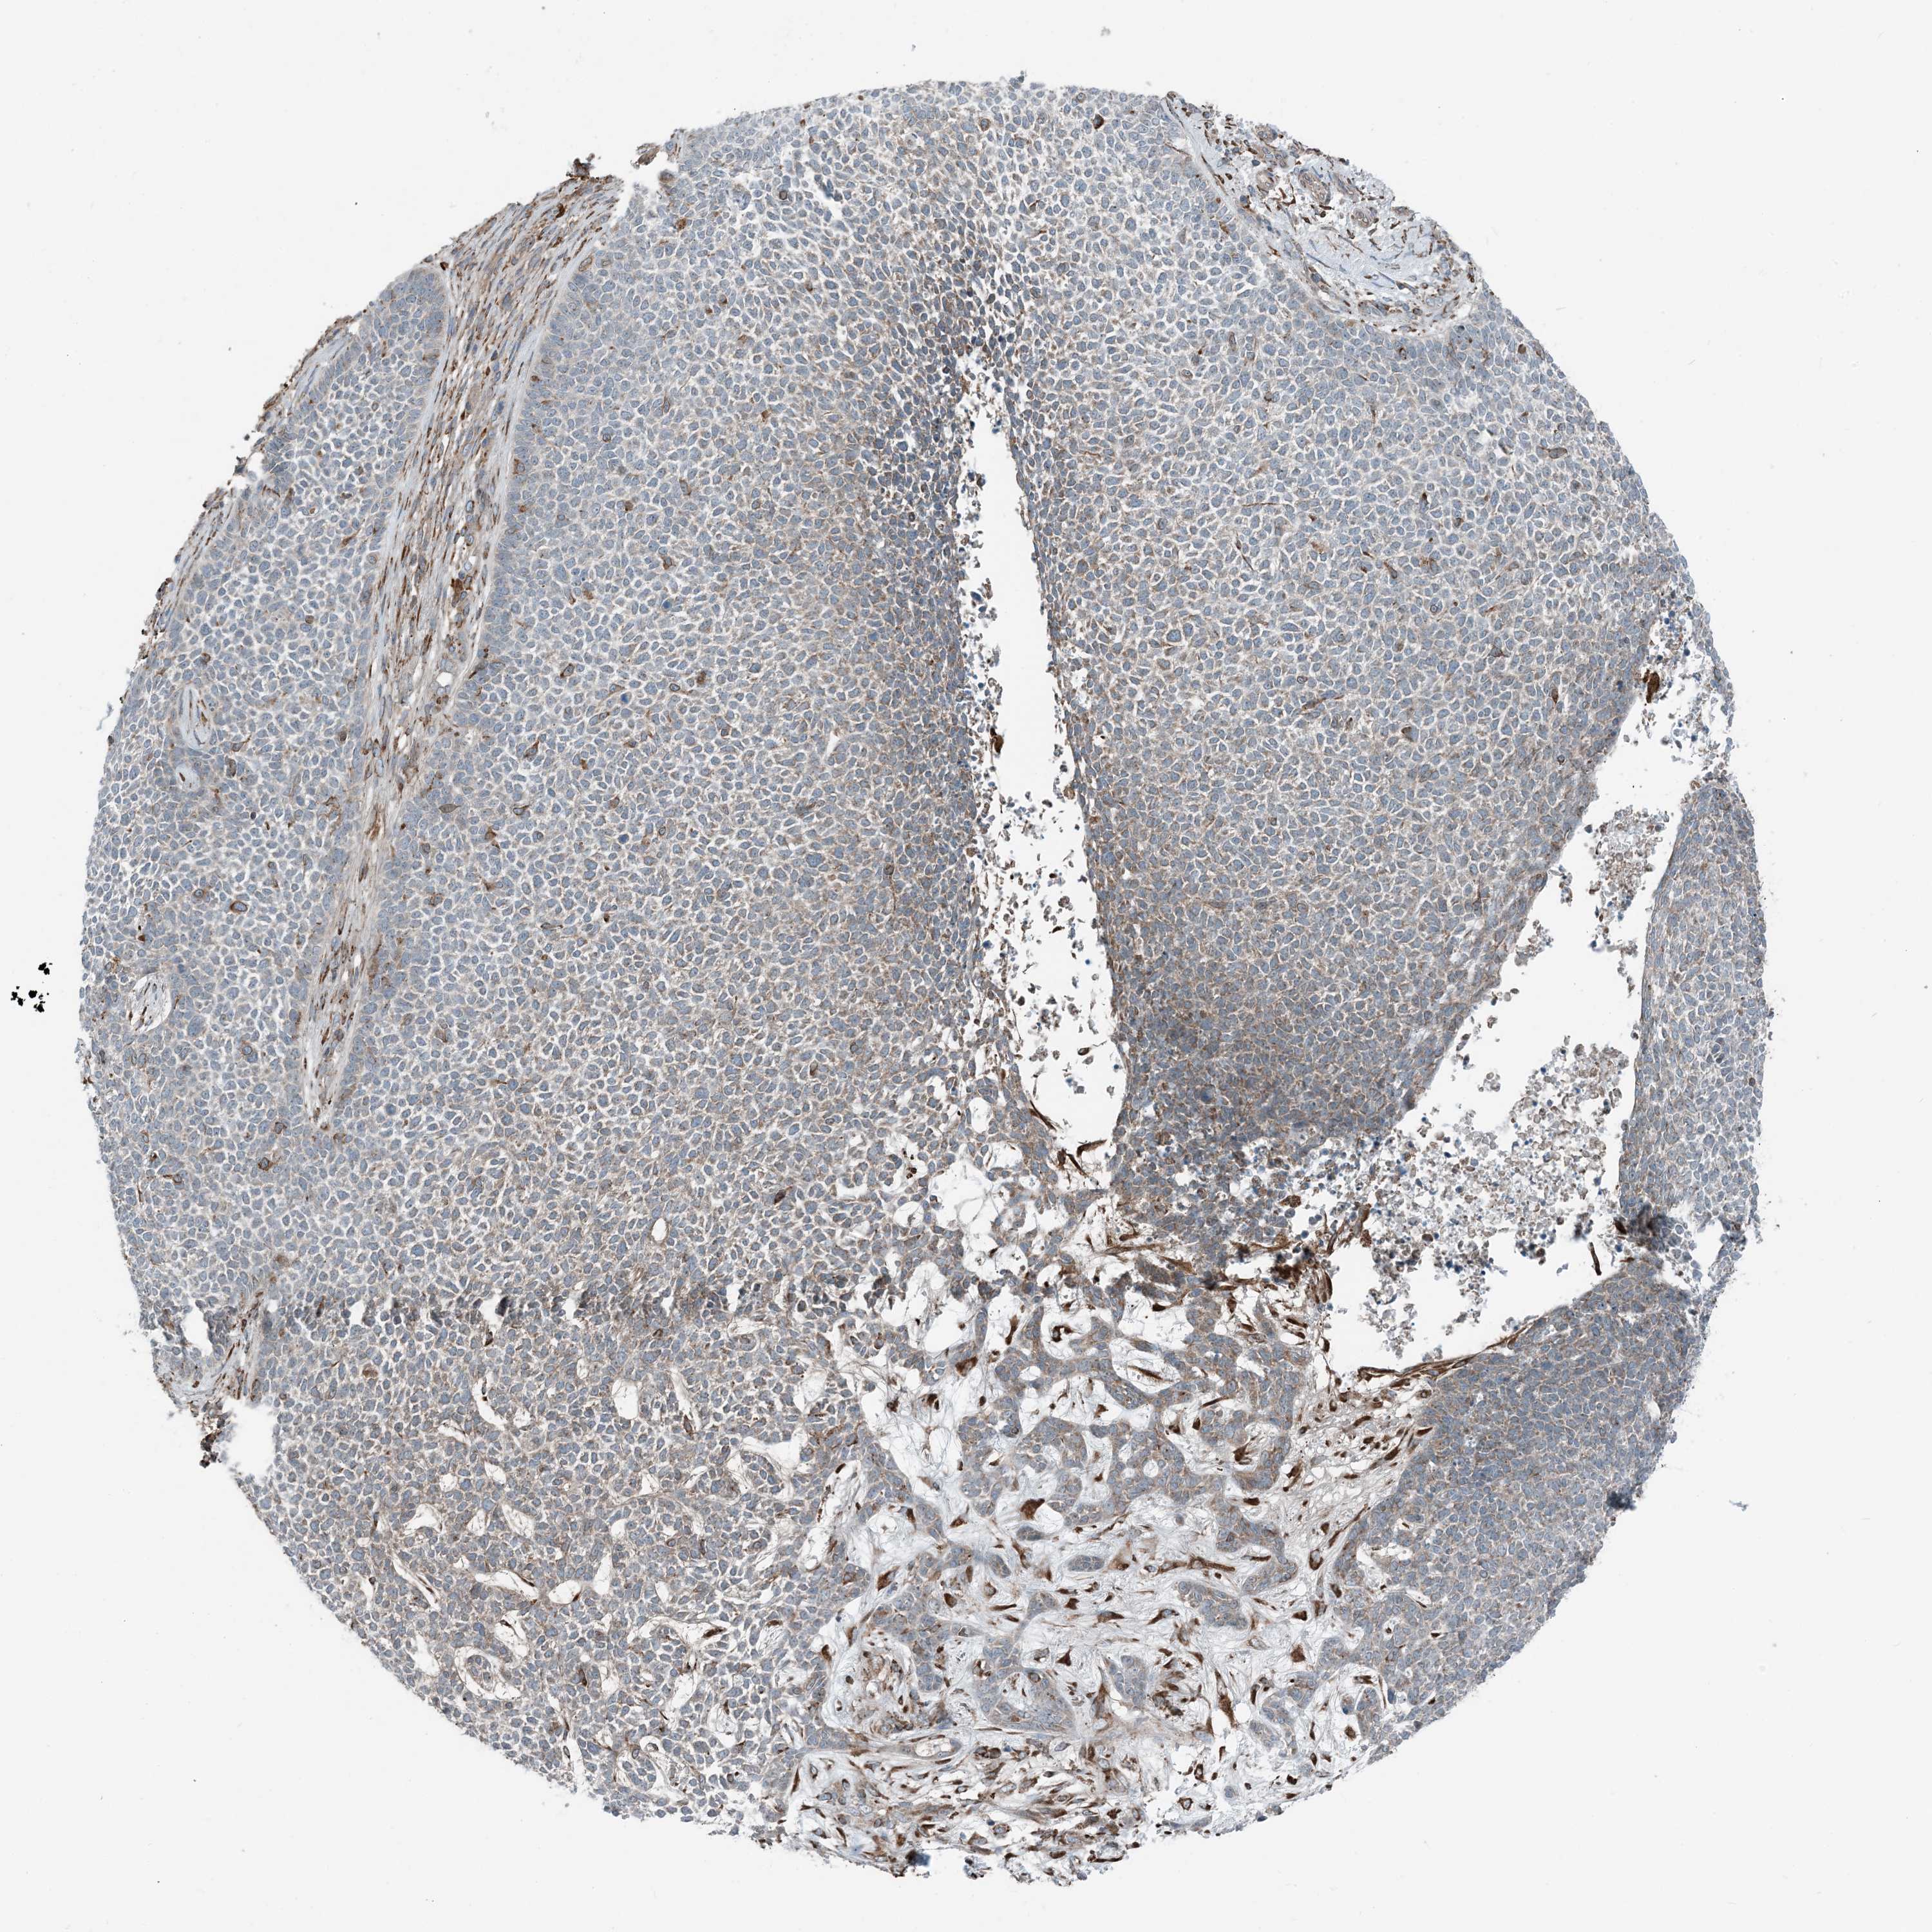

SKIN CANCER - Protein expressioni

A mouse-over function shows sample information and annotation data. Click on an image to view it in a full screen mode. Samples can be filtered based on level of antibody staining by selecting one or several of the following categories: high, medium, low and not detected. The assay and annotation is described here.

Each image is clickable and will lead to virtual microscopy that enables deeper exploration of all samples and also displays staining intensity scores, fraction scores and subcellular localization as well as patient and tissue information for each sample.

Antibody HPA035444

Staining

High

Medium

Low

Not detected

Intensity

Strong

Moderate

Weak

Negative

Quantity

>75%

75%-25%

<25%

None

Location

Nuclear

Cytoplasmic/membranous

Cytoplasmic/membranous,nuclear

Squamous cell carcinoma, NOS